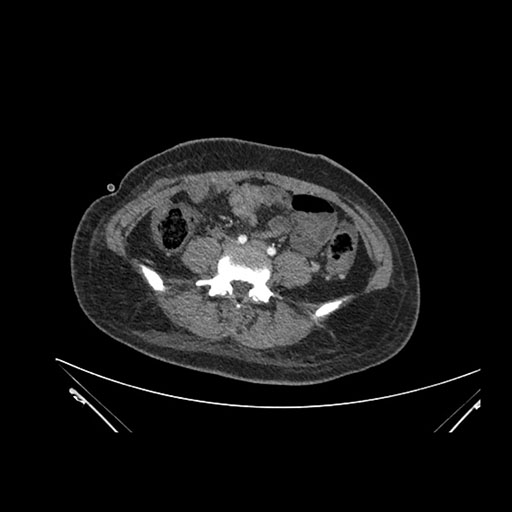

Imaging Analysis

Look through the patient's CT scan to identify any areas of concern for the necessary procedure.

Axial Venous

Based on initial findings, which issue(s) would you be most concerned about?